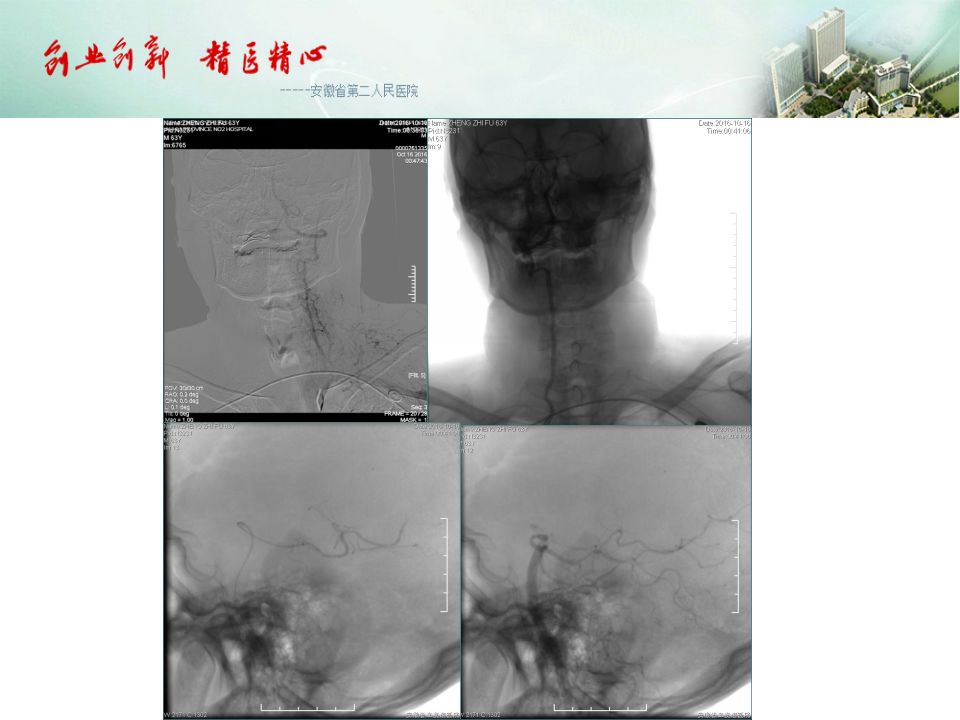

今天为大家分享的是“强生医疗CNV-神经介入专栏”第五十一期,由安徽省第二人民医院神经内科陈长春主任医师带来的“急性缺血性脑卒中超早期治疗--通与不通的哲学思考”精彩PPT,欢迎观看。文章仅代表作者个人观点,如有不同见解,欢迎同道斧正!